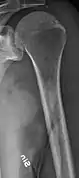

Medical imaging

The diagnostic examination of a person with suspected multiple myeloma typically includes a skeletal survey. This is a series of X-rays of the skull, axial skeleton, and proximal long bones. Myeloma activity sometimes appears as "lytic lesions" (with local disappearance of normal bone due to resorption) or as "punched-out lesions" on the skull X-ray ("raindrop skull"). Lesions may also be sclerotic, which is seen as radiodense.[70] Overall, the radiodensity of myeloma is between −30 and 120 Hounsfield units (HU).[71] Magnetic resonance imaging is more sensitive than simple X-rays in the detection of lytic lesions, and may supersede a skeletal survey, especially when vertebral disease is suspected. Occasionally, a CT scan is performed to measure the size of soft-tissue plasmacytomas. Nuclear Medicine Bone scans are typically not of any additional value in the workup of people with myeloma (no new bone formation; lytic lesions not well visualized on nuclear bone scan).